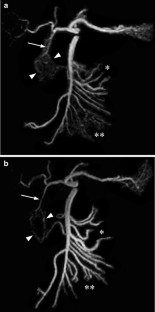

Fig. 1

Fig. 2

Fig. 3

Fig. 4